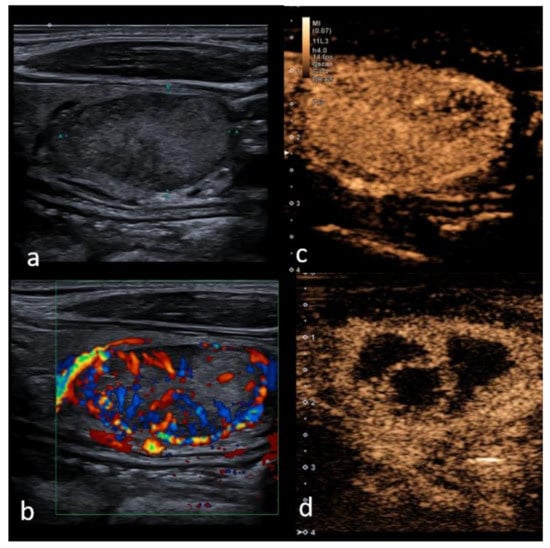

Figure 2. Right lobe heterogeneous lesion, TIRADS 4, Bethesda 5, Papillary cancer (a)—B mode hypo-echogenicity of the structure with cystic components; (b) Color Doppler shows hypervascularity in one part of the lesion, (c) contrast enhancement is heterogeneous with areas of low vascularization suggestive of malignancy and (d) confirming quantitative difference within the malignant tumor parts (yellow—necrotic areas, blue—intense enhancement and slow wash-out curve).

3.4. Thyroid Cancer in CEUS

There are several known subtypes of thyroid cancer, the most commonly described pattern of malignancy being a low enhancement on CEUS—particularly due to lack of blood supply and insufficient neovascularization, as well as interstitial fibrosis, especially in the central parts [41,82]. Qualitative patterns on CEUS suggesting malignancy include incomplete ring enhancement, heterogeneous enhancement and wash-out in the late phases; furthermore, such parameters suggestive of malignancy in the quantitative analysis include polyphasic washout curves, early arrival time and shorter TTP [54] (see Figure 2).